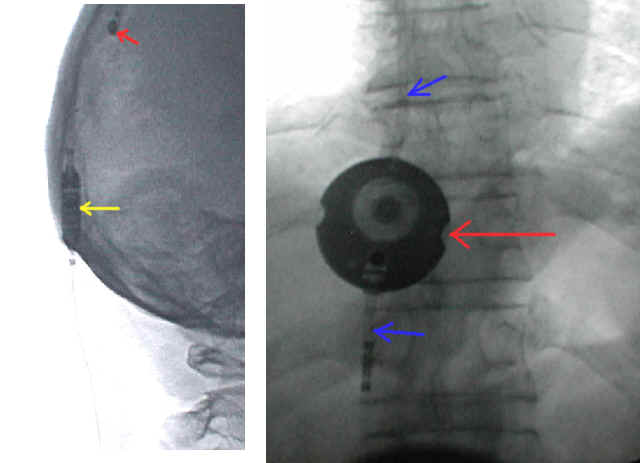

Diese beiden Abbildungen zeigen typische Lokalisationen von Ventilen am Körper: Links eine Röntgenaufnahme des Hinterhaupts. Der rote Pfeil markiert ein einstellbares Codmann-Hakim Ventil, das wenige Zentimeter oberhalb der Ohrspitze lokalisiert ist. Der gelbe Pfeil zeigt einen Miethke Shunt-Assistent der in Hohe des Ohransatzes etwa 3 - 4 cm hinter dem Ohr implantiert ist. Beide Implantate liegen außen auf dem Schädelknochen unter der Haut.

Die rechte Abbildung zeigt ein Miethke Dual-Switch Ventil, das an der vorderen Brustwand im Unterhautfettgewebe implantiert wurde (roter Pfeil). Mit ewtas Phantasie können Sie auch die Schläuche, die vom Ventil abgehen (mit blauen Pfeilen markiert) erkennen.